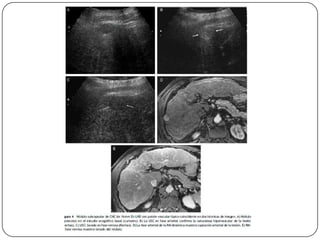

Auxiliares de diagnóstico

 USG

 Imágenes hipoecoicas, encapsuladas y con sombra

acústica, aunque en ocasiones aparecen como

alteraciones inespecíficas de la ecogenicidad, por

lo que resulta difícil diferenciarlas del daño

hepatocelular crónico.

 Sensibilidad (60-80%), Especificidad (45-96%)

 La sensibilidad en el CH alcanza 86%, pero en

lesiones menores de 2 cm es baja.

 Cada 6 meses en pacientes hepatópatas

 RM

 No utiliza contraste intravenoso

 Es más eficaz que la TC para diferenciar el CH de

nódulos de regeneración

 TAC

 Sensibilidad del 68% con especificidad de 93%, se

utiliza para precisar las alteraciones vistas en el

usg.